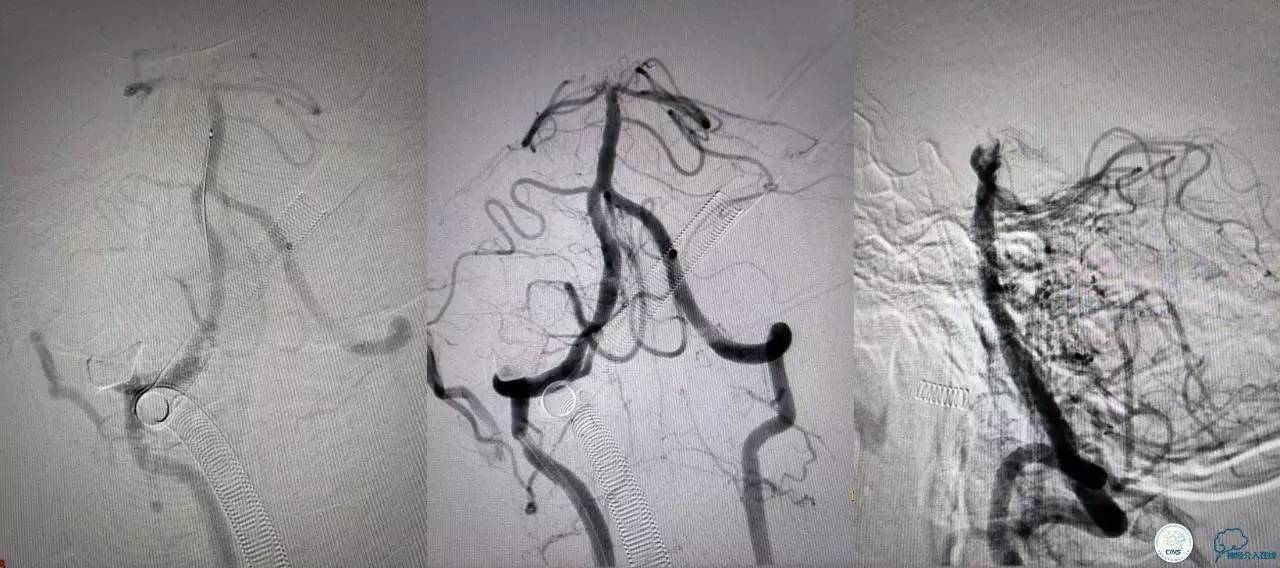

好大的血栓,支架释放后,血管无复流,拉一把!

没错,没看错!血管告捷实现再通,术中取栓的栓子如下。

术后

术后生命体征平稳,告捷撤呼吸机,肌力较前好转,复查头颅CT:

右侧丘脑高密度影,右侧枕叶可能也有梗死,祈祷慢慢恢复吧!